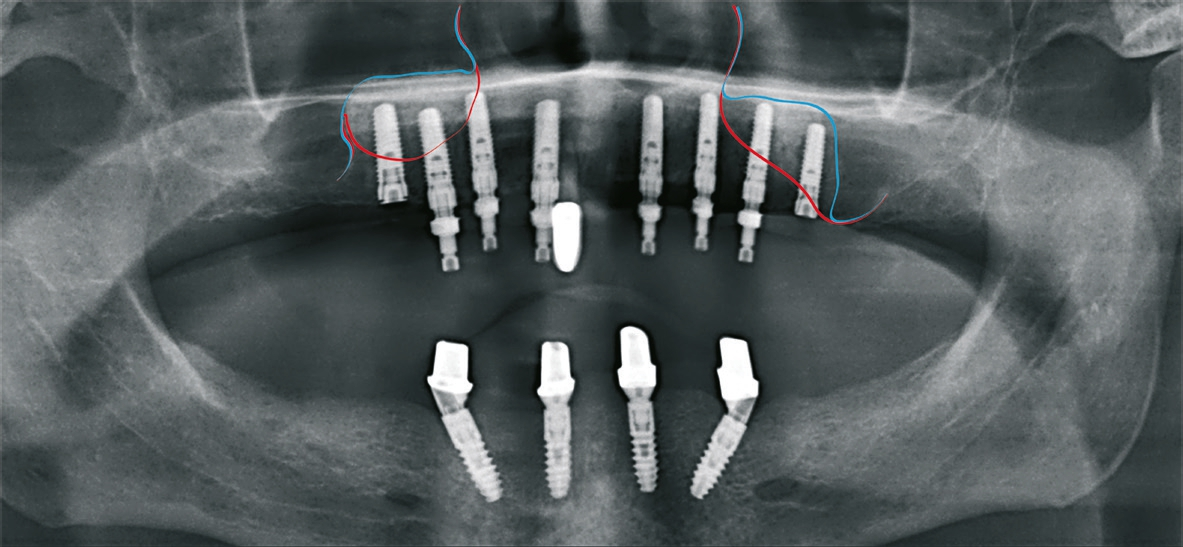

Patient 3: weiblich, 62 Jahre alt, Anamnese: unauffällig; spezielle Anamnese: Zustand nach chronischer schwerer Parodontitis; Diagnose: nicht erhaltungswürdiger Zahn 16, Freiendsituation. Knochenersatzmaterial: maxgraft® (botiss) (Abb. 13 bis 15).

Dr. van Orten